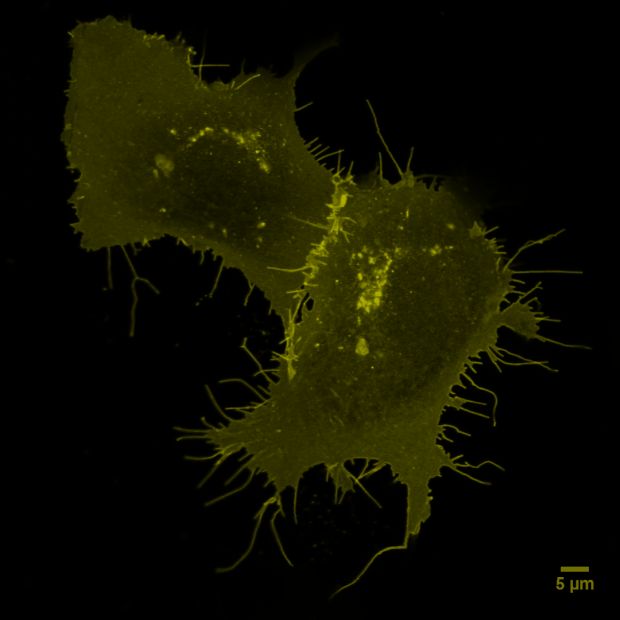

Foto: Immunfluoreszenz-Aufnahme der Lunge eines Patienten mit schwerem COVID-19: In dem stark geschädigten Lungengewebe sammeln sich Fresszellen (Makrophagen, rot) an. Grün angefärbt sind Bindegewebszellen (Fibroblasten). Foto: Uniklinik RWTH Aachen | Saskia von Stillfried